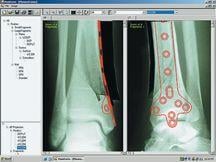

One such solution aiding surgeons is OrthopedicPACS, which combines TraumaCad (Orthocrat Ltd.) planning software with NovaRad’s NovaPACS software and imaging accessories, integrating patented Ortho tools with a NovaPACS workstation. TraumaCad enables advanced orthopedic surgical planning through precise manipulation of soft-copy images and application of fixation and prosthetic systems. It also includes advanced modular deformity correction and pediatric packages.

TraumaCad is also available as part of the Fuji Synapse PACS offering, as a result of a recent agreement between Orthocrat and FUJIFILM Medical Systems USA. Now physicians simply log in to the integrated solution, access patient images through the PACS and drag and drop them into the TraumaCad workspace. Completed surgical plans are then saved to the Synapse archive along with other patient files.

Extending beyond basic orthopedic planning, OrthoWorks ProPlanner provides support for deformity corrections, trauma and customized planning methodologies that mimic orthopedic workflow. In challenging deformity and trauma corrective cases, for example, image cutting allows surgeons to cut and reposition fractured bone fragments to visualize potential surgical changes. In converse circumstances, Image stitching allows users to stitch together two or more images using a number of methods to ensure that cases requiring long film X-rays can still be digitally planned without the need for expensive stitching hardware. OrthoWorks ProPlanner also incorporates Cedara’s unique ImageSnap Technology that enables automatic measurements with suggested implant selection and placement.